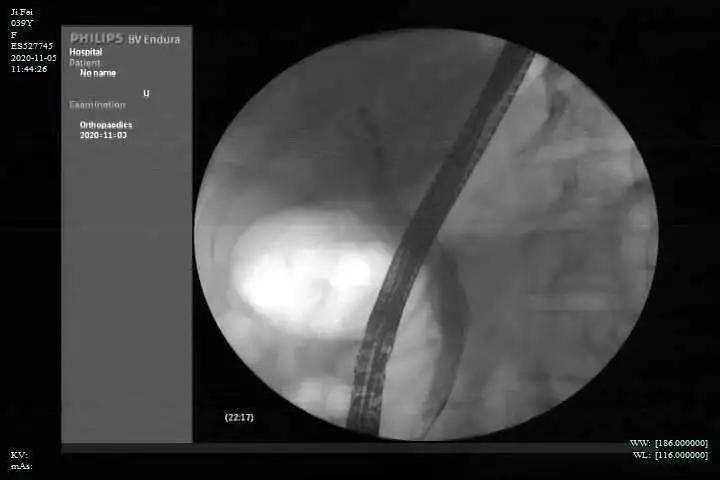

根据经验判断,施女士的胆总管结石符合 ERCP 治疗指征。张筱凤果断地将施女士收治入院,当天中午就为施女士做了 ERCP 手术。

所谓 ERCP 手术,全称为「内镜下逆行胰胆管造影术」,通过类似于胃镜的内镜,经口达到胰管、胆管汇合入肠道的开口处,再进一步对胆管胰管诊断和治疗。最常见的胆管结石,就能通过 ERCP 手术进行碎石、取石,让部分患者避免开腹手术;胰腺、胆管肿瘤堵塞了胆管,也可以通过这个手术来消退黄疸,改善症状,为进一步手术创造条件。

张筱凤带领团队为施女士行 ERCP 取石术,用网篮取出一枚黄色结石,术毕置入无袢支架,过程十分顺利。次日,施女士的不良症状全部消失,病情稳定予以出院。出院时,施女士忍不住地说:「真所谓,病来如山倒,病去如抽丝。连省级医院都发现和治疗不来的疾病,竟然在市一医院可以解决」。